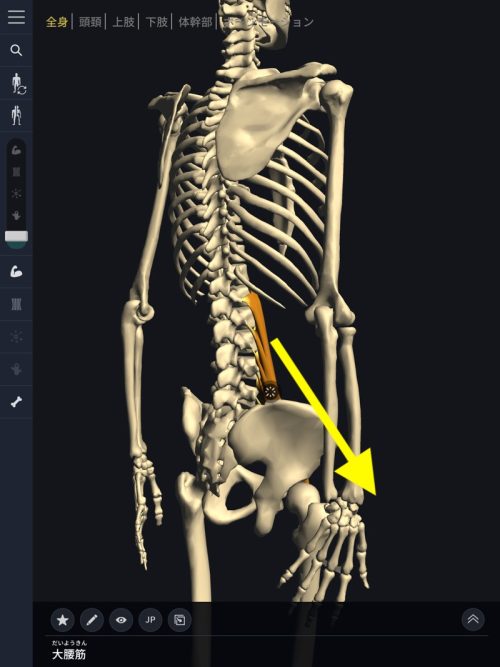

まずはこちらの図。大腰筋ですがこのように腰椎から足の付け根部分に接続されていますので、長時間座っていたり、立ち仕事の長い方、立ったりしゃがんだりを繰り返す方には負担が大きく硬直して縮むことで腰骨を足の方へ(下方向)引っ張ると先程説明しました。

大腰筋が硬直

硬直した腰筋が縮んで腰椎を下方へ圧迫